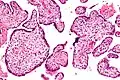

VUE can be of 2 types, low grade chronic villitis or high grade chronic villitis. Low grade chronic villitis involves less than 10 villi containing lymphocytes. Low grade chronic villitis can be either focal or multifocal. Focal has involved villi on only one glass slide, while multifocal has involved villi on at least two slides. High grade chronic villitis has more than 10 inflamed villi per focus. High grade chronic villitis is differentiated into diffuse and patchy. The term patchy is used if less than 30% of distal villi are involved. The term diffuse is used if more than 30% of distal villi are involved.

VUE has 2 prominent distinct patterns. Approximately 50% of the cases only involve the distal villi (mature intermediate and terminal villi) and do not involve the proximal stem villi, the anchoring villi embedded in the basal plate, and the chorionic plate. The second most common pattern (roughly 30% of VUE cases) involves the proximal stem villi (and possibly the chorionic plate) and the distal villi usually. This type of VUE is linked with foetal vascular obtrusive lesions (Obliterative Foetal Vasculopathy).[1][16]

VUE does not have specific clinical signs and symptoms suggesting diagnosis; but an analysis of the inflammatory filtrate can aid in diagnosis.[1] The composition of inflammatory infiltrate in VUE on a cellular level is primarily macrophages and lymphocytes. The relative proportions of cells vary case by case. The lymphocytes present in VUE are predominantly CD8+ T-cells then CD4. There is usually a ratio of 0.1 to 0.5 for CD4/CD8.[17][18] The macrophages present are mainly Mac387-, followed by CD68 and HAM56+. Class 2 major histocompatibility complex (MHC) antigens on macrophages are up-regulated at sites of VUE. Neutrophils should not be present at sites of VUE. VUE is a condition involving inflammation and not infection. High numbers of neutrophils are present in infectious villitis and not VUE.[1][14]

Histomorphologically, VUE is characterized by a lymphocytic infiltrate of the chorionic villi without a demonstrable cause. Plasma cells should be absent; the presence of plasma cells suggests an infective etiology, e.g. CMV infection.

Intermed. mag.